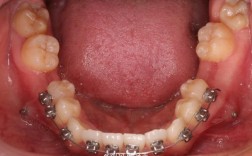

- 初期排齐:利用拔牙间隙,将拥挤的前牙(如侧切牙、尖牙)向远中移动,排齐下颌前牙段;

- 中期调整:通过弓丝加力(如滑动法、关闭曲法),逐渐关闭拔牙间隙,同时控制下颌磨牙的支抗(防止磨牙前移),确保间隙被前牙和后牙合理分配;

- 精细调整:间隙关闭后,进行咬合精细调整,包括牙齿的垂直高度、邻接触点、颌曲线等,确保咀嚼功能稳定。